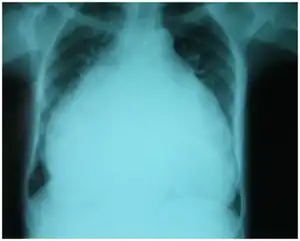

Chest-Xray: enlarged heart in TR and mitral valve disease